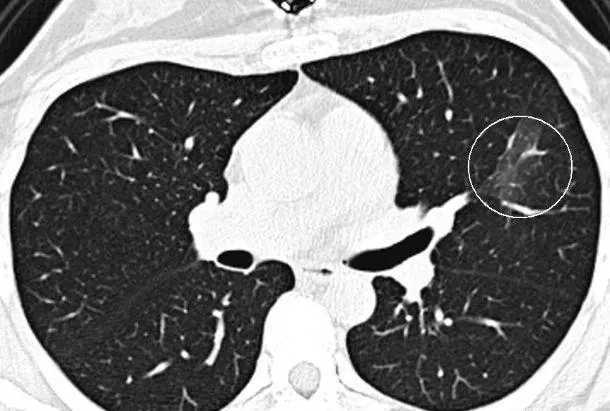

肺原位腺癌指的是发生在支气管或肺上皮层,并且没有突破基底膜的腺癌。肺原位腺癌一般肿瘤较小,基本上直径都在1cm以内,CT上大多数为纯磨玻璃结节或含实性成分的混合磨玻璃结节。在TNM分期中,肺原位癌为0期癌,属于极早期。即便不手术,这类肿瘤细胞非常惰性,贴壁生长,生长缓慢,很多人随访数年,结节并没有明显增大,部分人结节在数年后才加速增长。所以,肺原位癌不用担心短期内出现快速生长,甚至转移到其他地方。治疗上只需要在腔镜下手术切除就可以了,生长在周边的肺结节仅需要做肺段切除或楔行切除,可以最大程度的保留肺组织。肺原位腺癌术后不需要任何后续治疗,5年生存率接近100%。